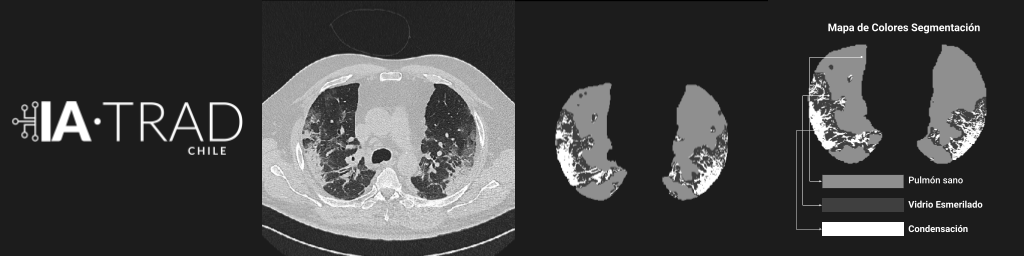

Apoyo al diagnóstico para COVID-19